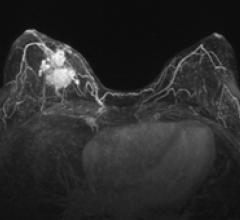

October 14, 2011 – Positioning breast cancer patients on their stomachs rather than their backs for radiotherapy could lead to better outcomes, according to a radiation oncologist who was among several clinical experts speaking in front of more than 500 oncology professionals about advances in cancer care at a symposium in Miami Beach, Fla., last week.